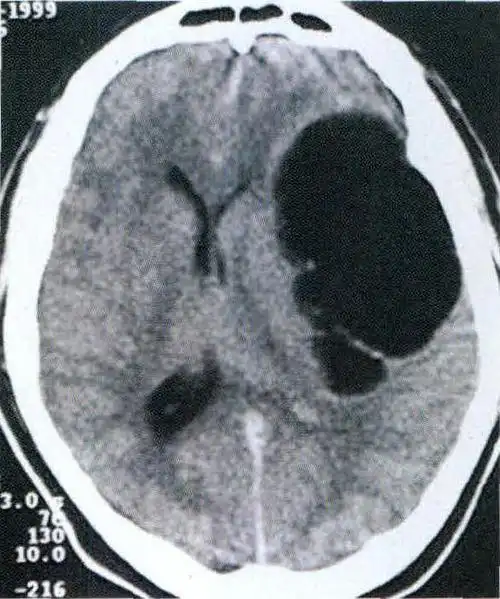

脑囊虫也导致三叉神经痛!罕见

(图) -1-2 左颞叶脑包虫病